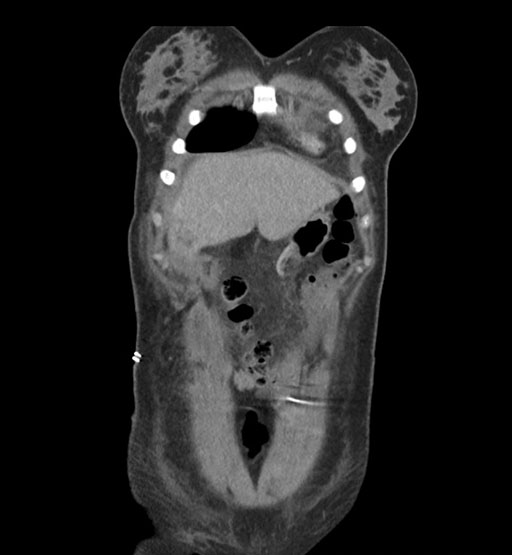

Coronal Arterial

Coronal Venous